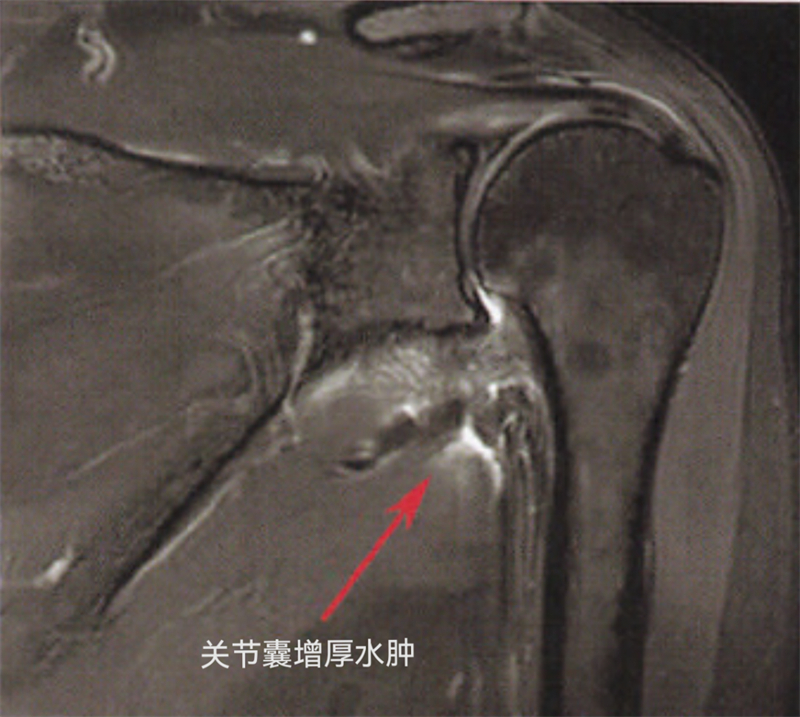

肩周炎俗称“五十肩”,顾名思义,常发生的年龄为50岁左右,也叫“冻结肩”或“粘连性肩关节囊炎”,就是说肩关节就像是被冻结住一样。主要发生在肩关节周围的关节囊,关节囊增厚、挛缩、水肿继发纤维化,弹性下降,导致肩关节被增厚的关节囊厚厚地包裹住,无法活动。

运动医学的医生有两个传家宝,一个是查体,另一个是看核磁共振。医生可以通过判断患者主动活动和被动活动时肩关节活动的受限程度,通过特殊查体,了解肩关节肩袖各个肌肉的功能情况和某些特定动作下的疼痛特点,用以判断患者是否合并肩袖撕裂、撞击等。医生再通过详细询问病史,了解是否有外伤以及肩周炎的高危因素。另外,运动医学医生通过核磁共振除了可以判断鉴别是否合并肩袖撕裂外,还可以清晰立体地看出肩关节囊增厚水肿的范围,判断肩周炎疾病的进展程度,需要药物保守功能康复锻炼还是需要手术治疗。